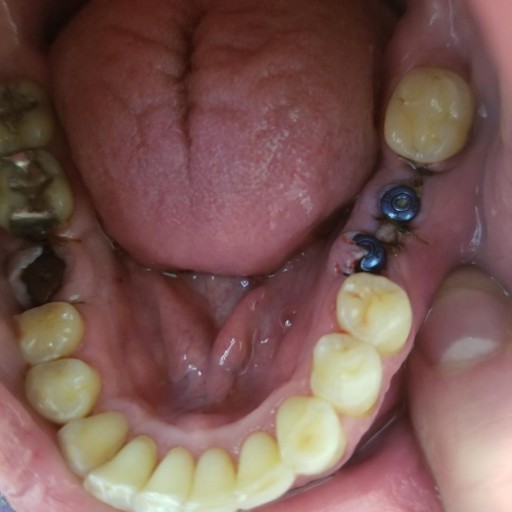

Abutment came off!

Hello there! My father just got a dental implant two days ago. Today, he felt his abutment getting loose while he was eating. After a bit, the abutment came off. What do we do now? Thanks in advance!

More than likely, it is not the abutment, but the healing cap that has come loose.  The abutment is not placed onto the implant until it is ready to be restored with a crown.  The healing cap can simply be replaced by the dentist.  It is a quick procedure that should not require dental anesthetic.